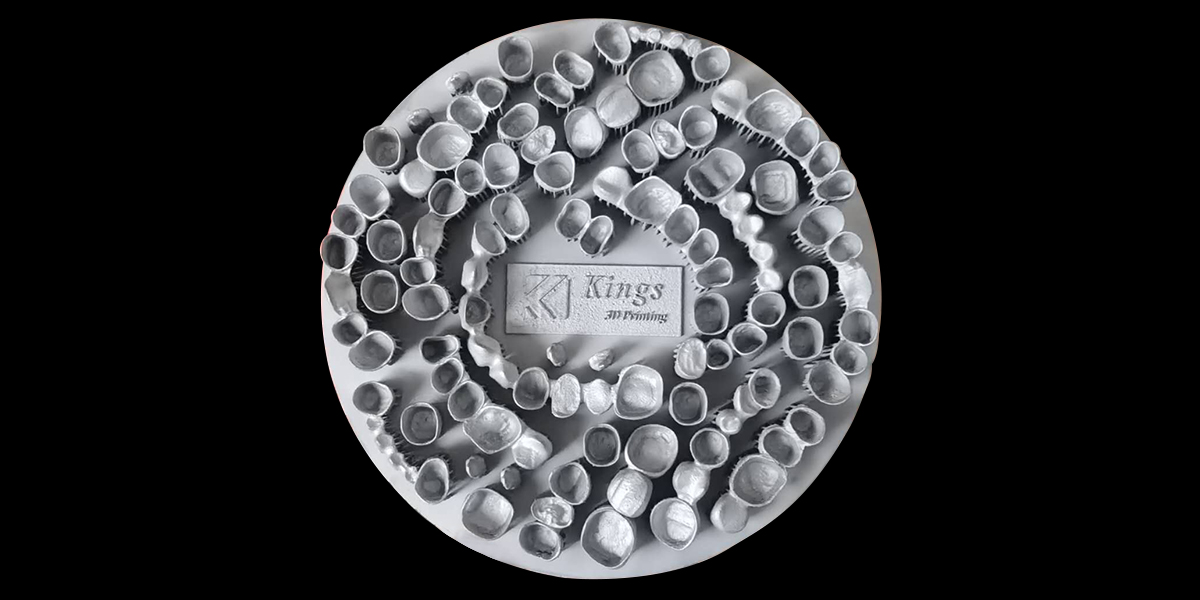

牙齒修復,也是通過3D打印患者的牙齒原型,根據其牙齒的殘缺部位來制作義齒。

不論是牙齒矯正還是修復,都屬于個性化定制,每個患者的牙齒形態都不一樣,通過傳統方法來制作這類牙模,時間和人力成本都很高。而3D打印可以批量化生產,在成本和效率方面都有強大的突破。